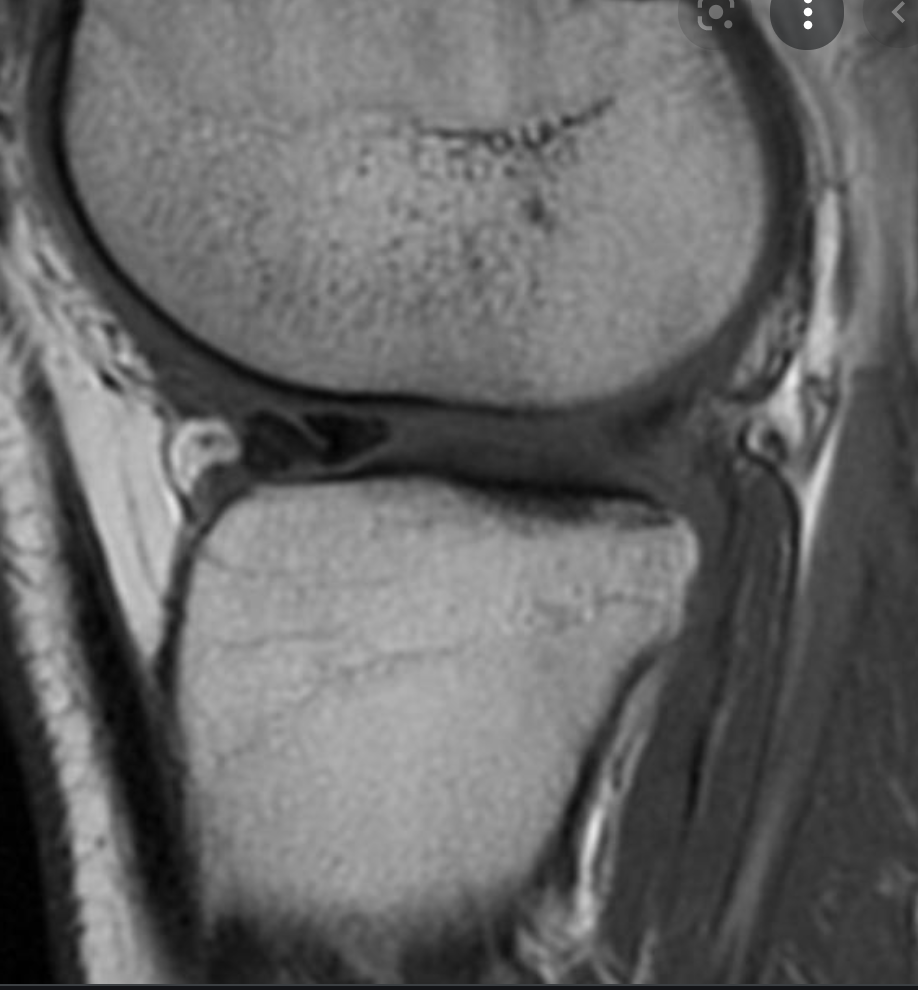

Meniscal root tear

Tear at the junction of the posterior horn medial meniscus and its attachment of the tibial eminence. This is known as the meniscal root.

Case Discussion

These tears are unusual and occur either as an acute injury in young patients or as a degenerative process in older patients. As the meniscus is reasonably well vascularised at the root, surgical repair is recommended in younger patients. In older patients with degeneration there is often associated chondral damage thus repair is more problematic and can fail.

Meniscal root tears are a type of meniscal tear in the knee where the tear extends to either the anterior or posterior meniscal root attachment to the central tibial plateau. They often tend to be radial tears extending into the meniscal root.

Radiographic features

MRI

Best assessed on T2 weighted sequences. When it involves the posterior root, medial root tears are easier to diagnose than lateral root tears.

On medial posterior root tears there is often 2:

shortening or absence of the root on sagittal images

vertical fluid cleft on coronal fluid-sensitive (T2) images

On posterior root radial tears of the lateral meniscus, the appearance may be similar to radial tears in other locations.

For root tears in general, sagittal imaging may demonstrate a meniscal ghost sign.

Other features include:

truncation sign on coronal images 4

features meniscal extrusion on coronal plane 4